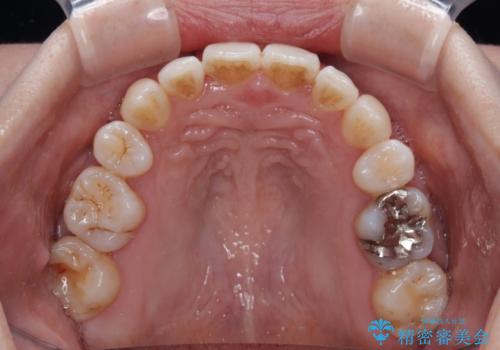

飛び出した上顎前歯と上下のデコボコ 片顎の抜歯によるワイヤー矯正

- 上下前歯のデコボコと、上顎の八重歯を気にして来院された患者様です。

下顎に対して上顎が前方にあり、第一大臼歯による咬合状態は上顎前突であったため、上顎のみ左右の第一小臼歯を抜歯し、ワイヤー装置にて矯正治療を行うこととしました。